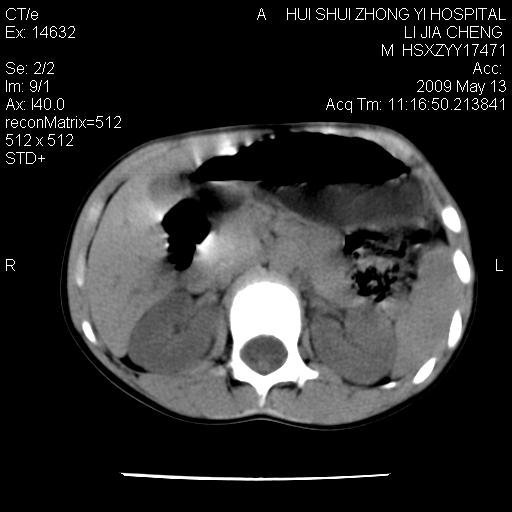

标题: PED1887:男性,6岁。反复脐周疼痛2年余。请各位老师看下腹 [打印本页]

标题: PED1887:男性,6岁。反复脐周疼痛2年余。请各位老师看下腹

该患者可自行好转,大小便未见异常,化验:便未见虫卵,血常规:wbc:8000;淋巴3600,中性45%

脂肪肉瘤可能性大,大血管边界不清,特别是腔静脉。不除外其他腹膜后肿瘤。

是不是有蛔虫哦,楼主图示块影前方肠管壁显著增厚,不除外慢性肠炎或肠壁占位,建议肠道准备后复查

来源于十二指肠水平部病变?建议行进一步检查。